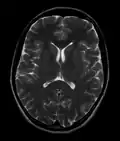

Normal axial T2-weighted MR image of the brain -

MRI image of the surface of the brain.